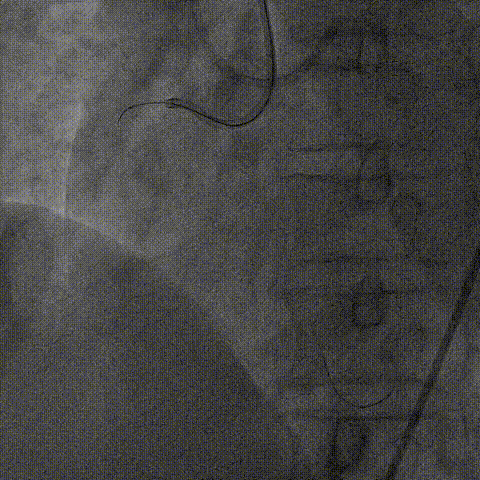

右冠PCI

逆向器械:

1、选择近段粗大间隔支;Finecross(150cm);Sion导丝surfing通过侧枝循环至右冠远段,跟进微导管后尝试UB3、Gaia3导丝至闭塞段远段与正向导丝重叠,但闭塞段钙化可能导丝逆向导丝无法进一步前进突破。

策略转换:

1、逆向导丝无法进一步前进突破后及时转换策略,决定以逆向导丝为路标,操控正向导丝定向穿刺逆向导丝。

2、正向升级为Gaia3导丝多投照体位穿刺并靠近逆向导丝,但无法进入远端真腔,升级为Pilot200导丝试图尽量考虑血管真腔加强支撑力后启动Reverse-Cart,多体位操控后导丝幸运进入血管远端真腔。